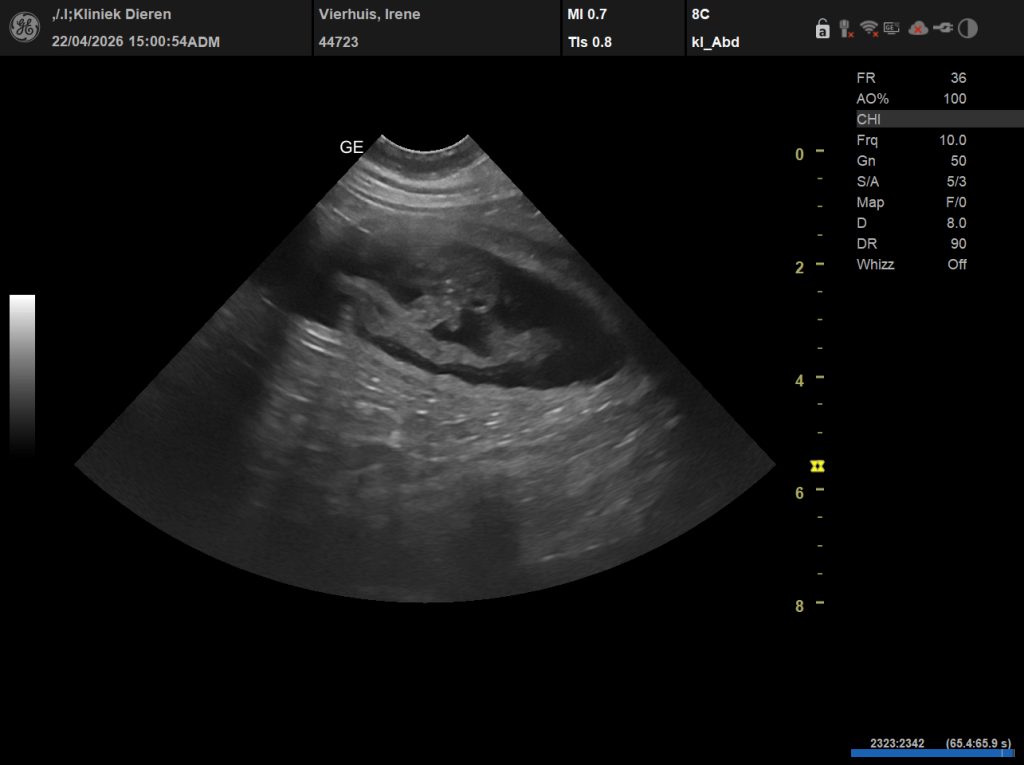

Tijdens de echo heeft de DA rond de tien vruchtjes gezien. Dat moment… dat scherm zien, hartjes zien, weten dat er leven groeit… dat vergeet je niet.